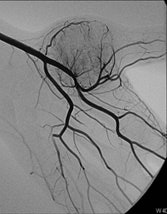

In the third year of my residency in 1982, I began to be attracted by the new way to perform interventions through percutaneous and endovascular approaches, and for a few months I went to the MD Anderson Center in Houston, Texas, U.S. There I took an important decision, which was that I would like to be completely involved in interventional radiology (IR), and with the great support of the CUN, this is what I have done for the rest of my professional life.